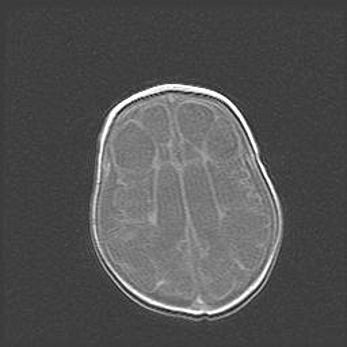

Сообщающаяся гидроцефалия. Кистозная энцефаломаляция головного мозга.

Возраст: 3 месяца 4 дня

Вес: 3100 г

Пол: женский

Окружность головы: 34 см

Срок гестации: 31 неделя

Кистозная энцефаломаляция головного мозга - одна из форм поражения головного мозга в детском возрасте. Характеризуется возникновением множественных и распространённых кист в коре, белом веществе и подкорковых образованиях головного мозга у плодов, новорождённых и детей раннего возраста. Развитие кистозной энцефаломаляции связано с внутриутробной асфиксией и гипотонией, родовой травмой, тромбозом синусов, пороками развития сосудов, инфекциями, сепсисом и другими причинами. Наиболее значимые инфекционные агенты: вирусы простого герпеса, цитомегалии, краснухи, токсоплазмы, энтеробактерии, золотистый стафилококк и другие.